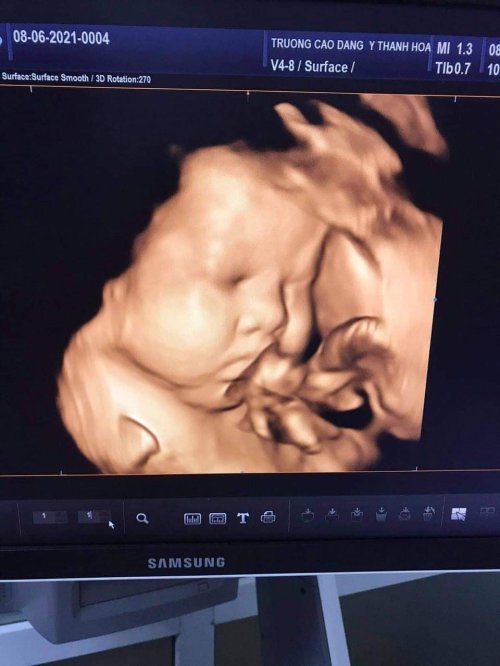

Khi mang thai, siêu âm cho nhiều giá trị chẩn đoán và giúp phát hiện những bất thường trong quá trình mang thai. Thông thường trong mỗi lần mang thai, tối thiểu sản phụ cần siêu âm 3 lần vào các mốc sau: 11-14 tuần, 18-22 tuần và 30 - 32 tuần.

- Siêu âm thai định kỳ là việc làm rất cần thiết để theo dõi quá trình mang thai và kịp thời phát hiện được các bệnh tiềm ẩn của thai nhi cũng như thai phụ. Siêu âm là phương tiện chuẩn đoán hình ảnh giúp đánh giá sức khỏe của phụ nữ mang thai. Đây cũng là một kỹ thuật an toàn, chính xác và đơn giản.

Tại Phòng khám đa khoa Cao đẳng Y tế Thanh Hoá quy tụđội ngũ y, bác sĩ giàu kinh nghiệm, trình độ chuyên môn cao. Cùng sự hỗ trợđắc lực của hệ thống trang thiết bị y tế hiện đại, đặc biệt là hệ thống máy siêu âm Accuvic A30 và máy siêu âm Volusun P8 sẽ giúp tầm soát dị tật thai nhi một cách hiệu quả nhất như: tim bẩm sinh, hội chứng DOWN...Ngoài ra phòng khám còn triển khai làm các xét nghiệm như: NIPT, DOUBLE test, TRIPLE test, tiểu đường.....